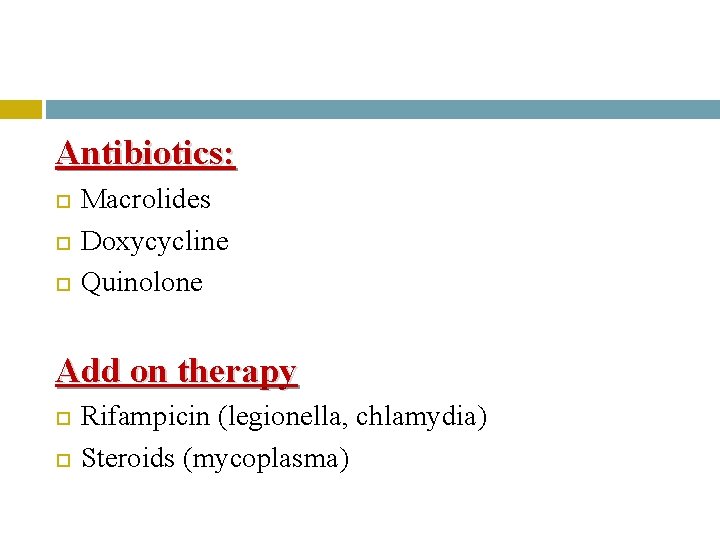

Antibiotics: Macrolides Doxycycline Quinolone Add on therapy Rifampicin (legionella, chlamydia) Steroids (mycoplasma)

Doses Erythromycin 500 mg/ 6 -hours Azithromycin 500 mg/24 hours Doxycycline 200 mg for the first dose Followed by 100 mg / 12 -hours Ciprofloxacin 400 mg/8 hours IV OR 750 mg orally /12 hours Levofloxacin 750 mg/24 hours Moxifloxacin 400 mg/24 hours Rifampicin 600 mg /12 hours

Duration It is recommended that treatment is continued for 2 – 3 weeks for fear that shorter periods may result in delayed resolution or relapse, particularly in those who are immunosuppressed or who have extensive disease.